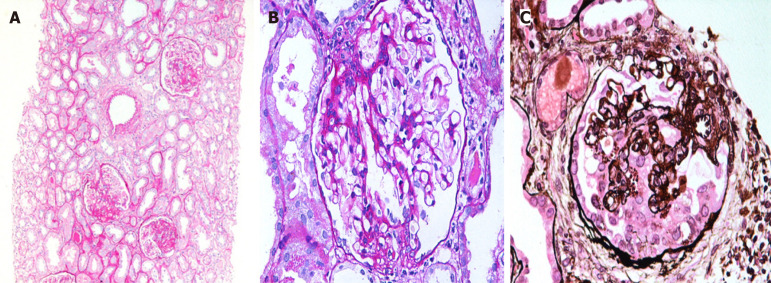

Abstract Image